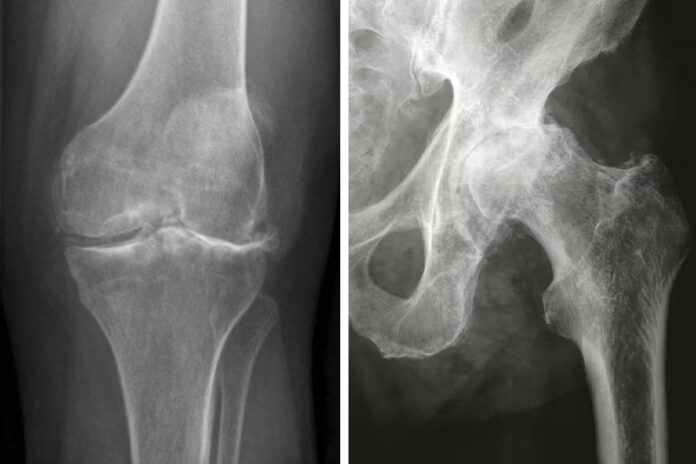

Επιβεβαίωση με απεικονιστικές εξετάσεις όπως ακτινογραφίες

Η οστεοαρθρίτιδα είναι μια εκφυλιστική νόσος των αρθρώσεων, η οποία χαρακτηρίζεται από σταδιακή καταστροφή του αρθρικού χόνδρου, αλλά και άλλων ανατομικών στοιχείων της άρθρωσης, όπως οι μηνίσκοι, οι σύνδεσμοι και ο αρθρικός θύλακος. Η πάθηση αυτή προκαλεί χρόνιο πόνο, φλεγμονή και μειωμένη κινητικότητα.

2. Ποια είναι τα κύρια συμπτώματα και πώς επιβεβαιώνεται η διάγνωση;